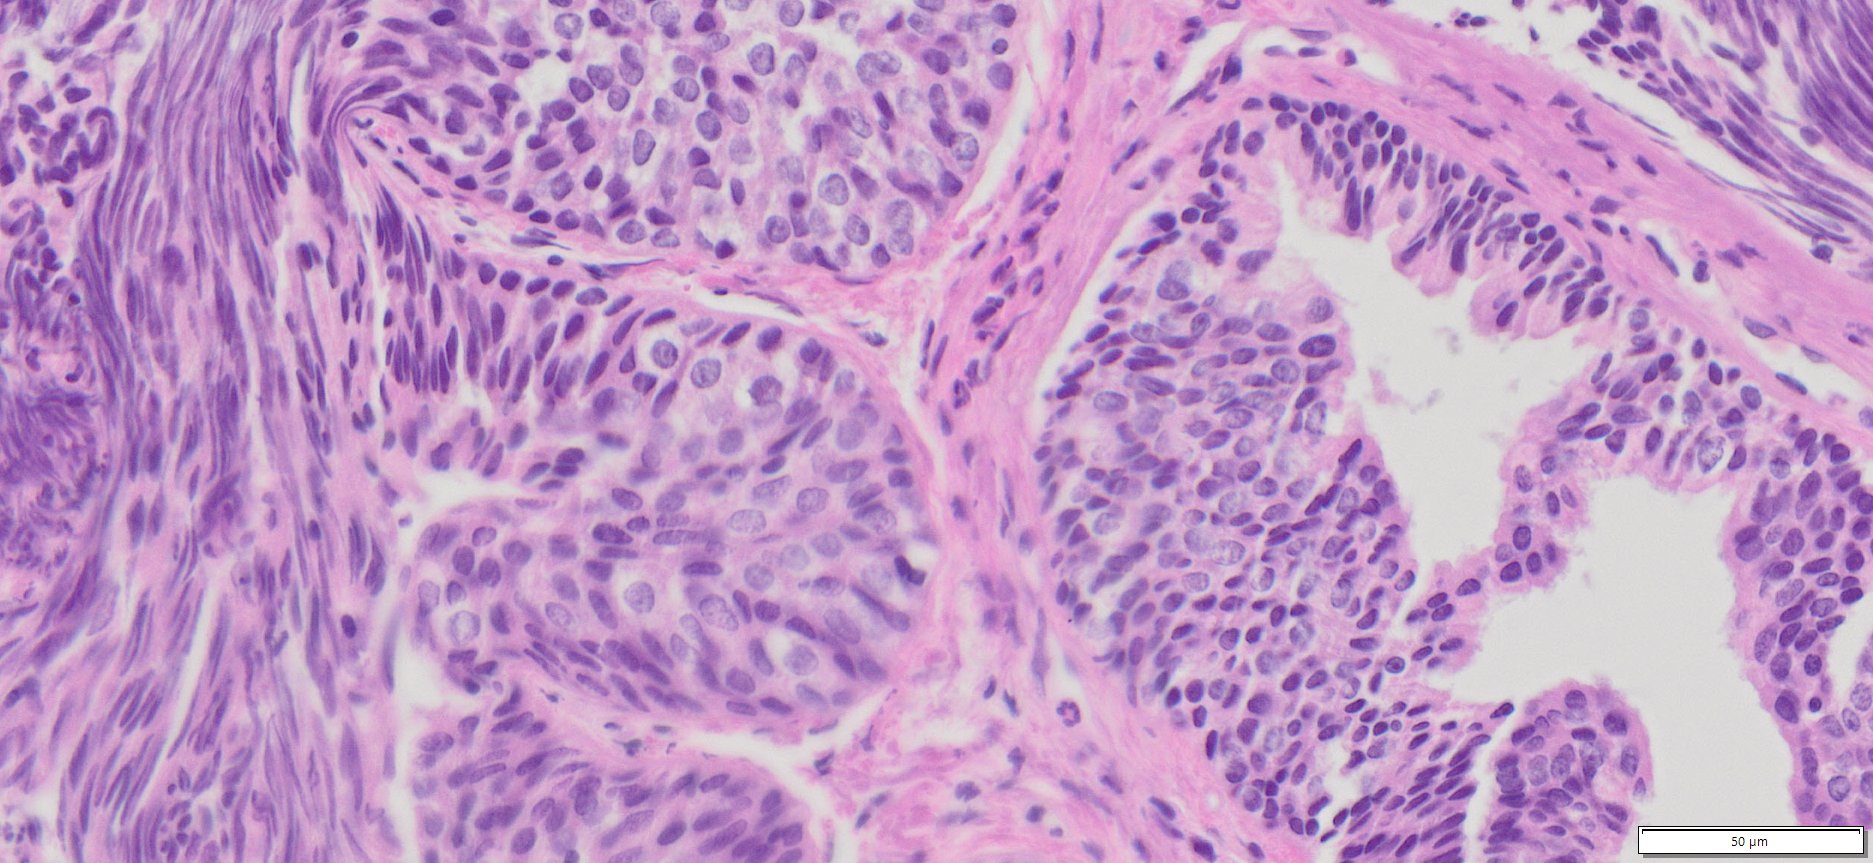

Description

| Tissue | Pathology Diagnosis | Gender/Age (year) | % Tumor area | Tumor Grade | TMN Stage | IHC Data |

| Human Rectum | Moderately differentiated colonic adenocarcinoma with 40% mucinous component | Male/59 | 20% | II | pT4apN1bpMx | NA |

Images for H&E Stain and IHC